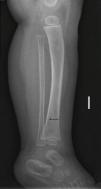

Niño de 12 meses, sin antecedentes de interés, que consulta por limitación para la deambulación de 24h de evolución, sin otra sintomatología acompañante. No historia de traumatismo ni cuadro catarral previo. En la exploración no se objetiva aumento de volumen articular, ni puntos dolorosos. Mantiene posición en reposo en flexo de cadera y rodillas, pero rechaza el apoyo de pie izquierdo en bipedestación. El resto de la exploración física es normal. Se realiza radiografía de tibia-peroné izquierda que muestra una fina línea de fractura en tibia distal solo en proyección lateral (figs. 1 y 2).

La fractura oculta, fractura de los primeros pasos o fractura de Toddler es una entidad propia de los niños menores de 3 años. Tras un traumatismo banal, el niño comienza con rechazo de la deambulación sin observarse, en la mayoría de los casos, otras alteraciones en la exploración física. En ocasiones, con una exploración minuciosa se puede apreciar un punto doloroso en la zona implicada. Radiológicamente es una fractura incompleta, no desplazada, de trayecto espiroideo muy fino, siendo el tercio distal de tibia, la región anatómica más frecuentemente afectada. Debido a sus características particulares, en ocasiones no se observa línea de fractura o solo es apreciada en una proyección radiológica1,2. Recientemente se ha propuesto la ecografía como método diagnóstico para confirmar la rotura cortical3.